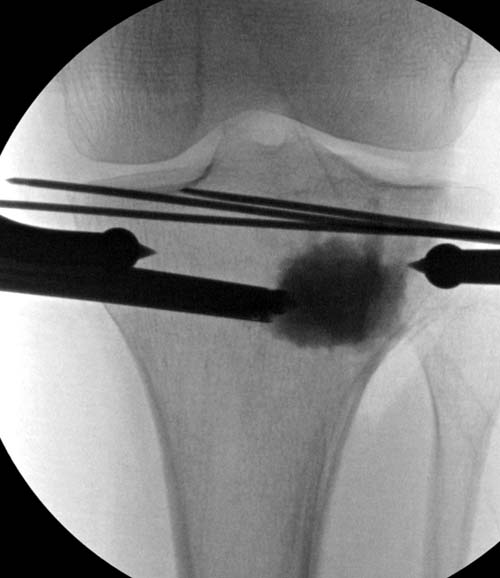

Re: Импрессионный перелом латерального мыщелка левой большеберцевой кости.

Устранение импрессии, костная аутопластика, остеосинтез опорной пластиной

оперировать вероятнее всего надо, импрессия приличная , думаю около 1,5 см, только вот она в задних отделах, преимущественно. Если ставить опорную пластину, то делать это нужно сзади, иначе никакой опорности, а задний котртекс по КТ похоже замят

Учитывая, что у пациента молодой возраст(судя по рентгенограммам,абсолютно показано восстановление суставной линии: подменисковый доступ,подъём импренированной части мыщелка, костная аутопластика, остеосинтез, решение вопроса с мениском (шов либо парциальная резекция)).

Как подсказывают, можно с противоположной стороны приподнять сустав и заполнить костный дефект. Параллельные винты создадут достаточную опору, но иногда buttress plate за счет диафиза создает дополнительную стабильность. Структуральный материал для профилактики от раннего коллапса, и пластическим материалом служит более твердый синтетический материал (Osteoset DBM) или аутокость.

Для лечения некоторых видов центральной импрессии (Schatzker III) можно применить методику Balloon tibioplasty, которая позволяет приподнять сустав без дополнительных доступов. Для информации здесь недавний пример, дефект заполнен жидкой формой композитного материала PRO-DENSE: http://www.wmt.com/prodense/product_overview.asp